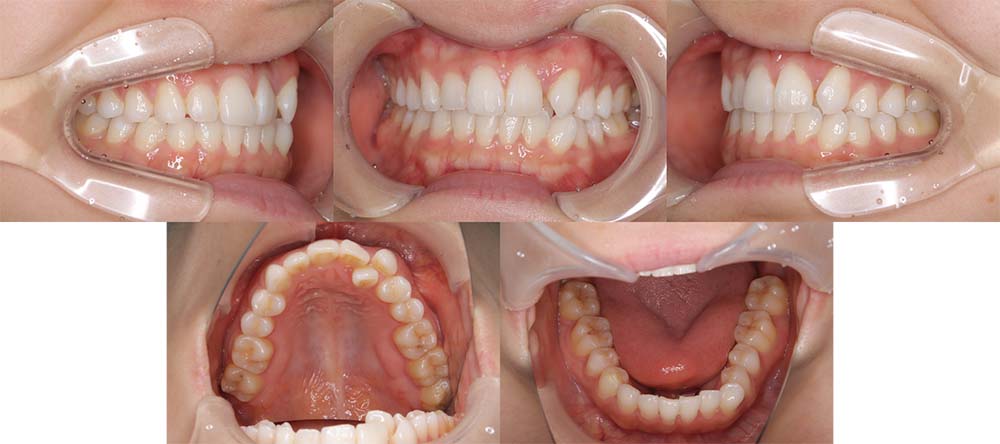

| 症例分類 | 叢生、上顎前突、口唇突出 |

| 診断名 | 下顎重度叢生を伴う骨格性上顎前突 |

| 主訴 | 歯並びが悪い、ものがよく噛めない、口元が気になる、歯科医師に勧められた |

| 年齢 | 22歳10ヶ月 |

| 性別 | 女性 |

| 抜歯部位 | 上下左右の第一小臼歯(4本) |

| 使用装置 | 表側のワイヤー装置 |

| 治療期間 | 2年2ヶ月 |

| 保定装置 | 固定式保定装置、取り外し式保定装置(8時間) |

| 費用 |

[検査・診断料] ¥49,500 [基本施術料] ¥792,000 [調整料] ¥4,400/回 [抜歯] ¥5,500/本 [保定装置] ¥55,000(税込) 抜歯や虫歯治療は他院にて費用が別途かかります。(抜歯¥4,000〜10,000/本)

下顎前歯重度叢生と上顎歯列の前方位、口唇閉鎖不全、口唇突出感があるため、上顎両側第一小臼歯と下顎両側第一小臼歯を抜去して治療を行いました。上顎前歯をしっかりと舌側移動しないといけなかったため矯正用アンカースクリューを使用しました。

前歯がしっかりと舌側移動できたため、口唇閉鎖不全が改善され口唇突出感もなくなり、問題なく咬合させることができました。